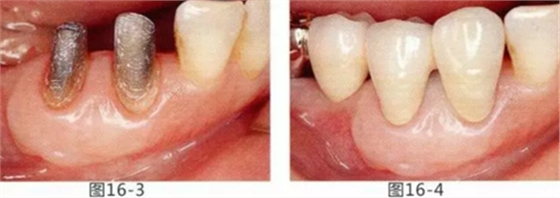

圖16-3 獲得了足夠附著齦,可以抵抗刷牙等外部刺激。

圖16-4 獲得充分附著齦,易清潔的狀態(tài)。修復(fù)體之間的鼓形間隙大小均一也使清潔性得到提升。

圖16-5 佩戴最終修復(fù)體3年后的狀態(tài)。

圖16-6 佩戴最終修復(fù)體11年后的狀態(tài)。無牙齦萎縮保持著安定狀態(tài)。